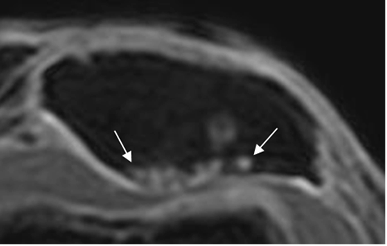

Fig 172. Condromalacia patelar grado IV.

RM axial en 3D T1 STIR. Pérdida completa del cartílago articular en la parte externa, con lesión osea asociada de la patela.